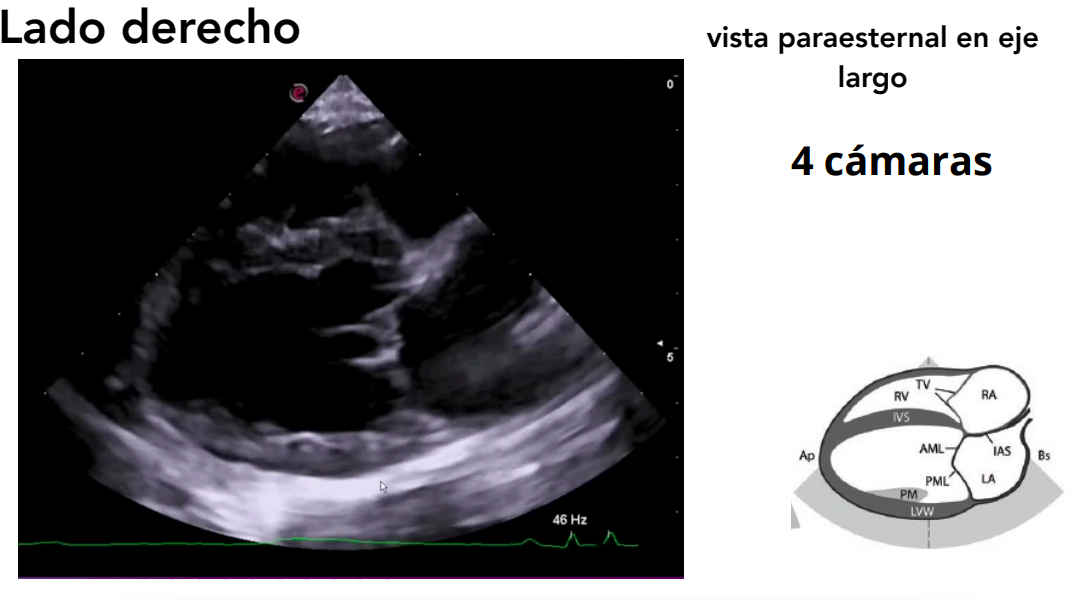

1. Lado derecho

Posición: decúbito lateral derecho.

- El transductor se coloca en el 4º-5º espacio intercostal, a 1–5 cm del borde esternal. Por eso se llama paraesternal.

- Se obtienen vistas paraesternales (ejes largos y cortos).

Ejes:

- Largo (longitudinal): del eje base–ápex.

- Corto (transversal): perpendicular al eje largo.

Vista paraesternal en eje largo

- 4 cámaras y 5 cámaras (incluye tracto de salida del VI).

- Evaluación de:

- Válvulas mitral, tricúspide y aórtica.

- Regurgitaciones valvulares.

- Defectos en septos interatrial e interventricular.

Doppler color: muestra regurgitaciones.

Doppler espectral: analiza velocidades de flujo.